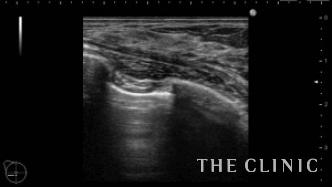

この方は2ヵ月前にヒアルロン酸注入を受けられていますが、除去したいとのご希望でご来院されました。エコーにて、乳腺下に一塊のものと蜂の巣状、皮下にも蜂の巣状のヒアルロン酸のしこりを確認しました。

しこりを穿刺し、ヒアルロニダーゼを注入して吸引除去します。

左)吸引後、しこりは消失しました。

右)除去したヒアルロン酸です。

ヒアルロン酸注入によるしこりのエコー診断カルテ